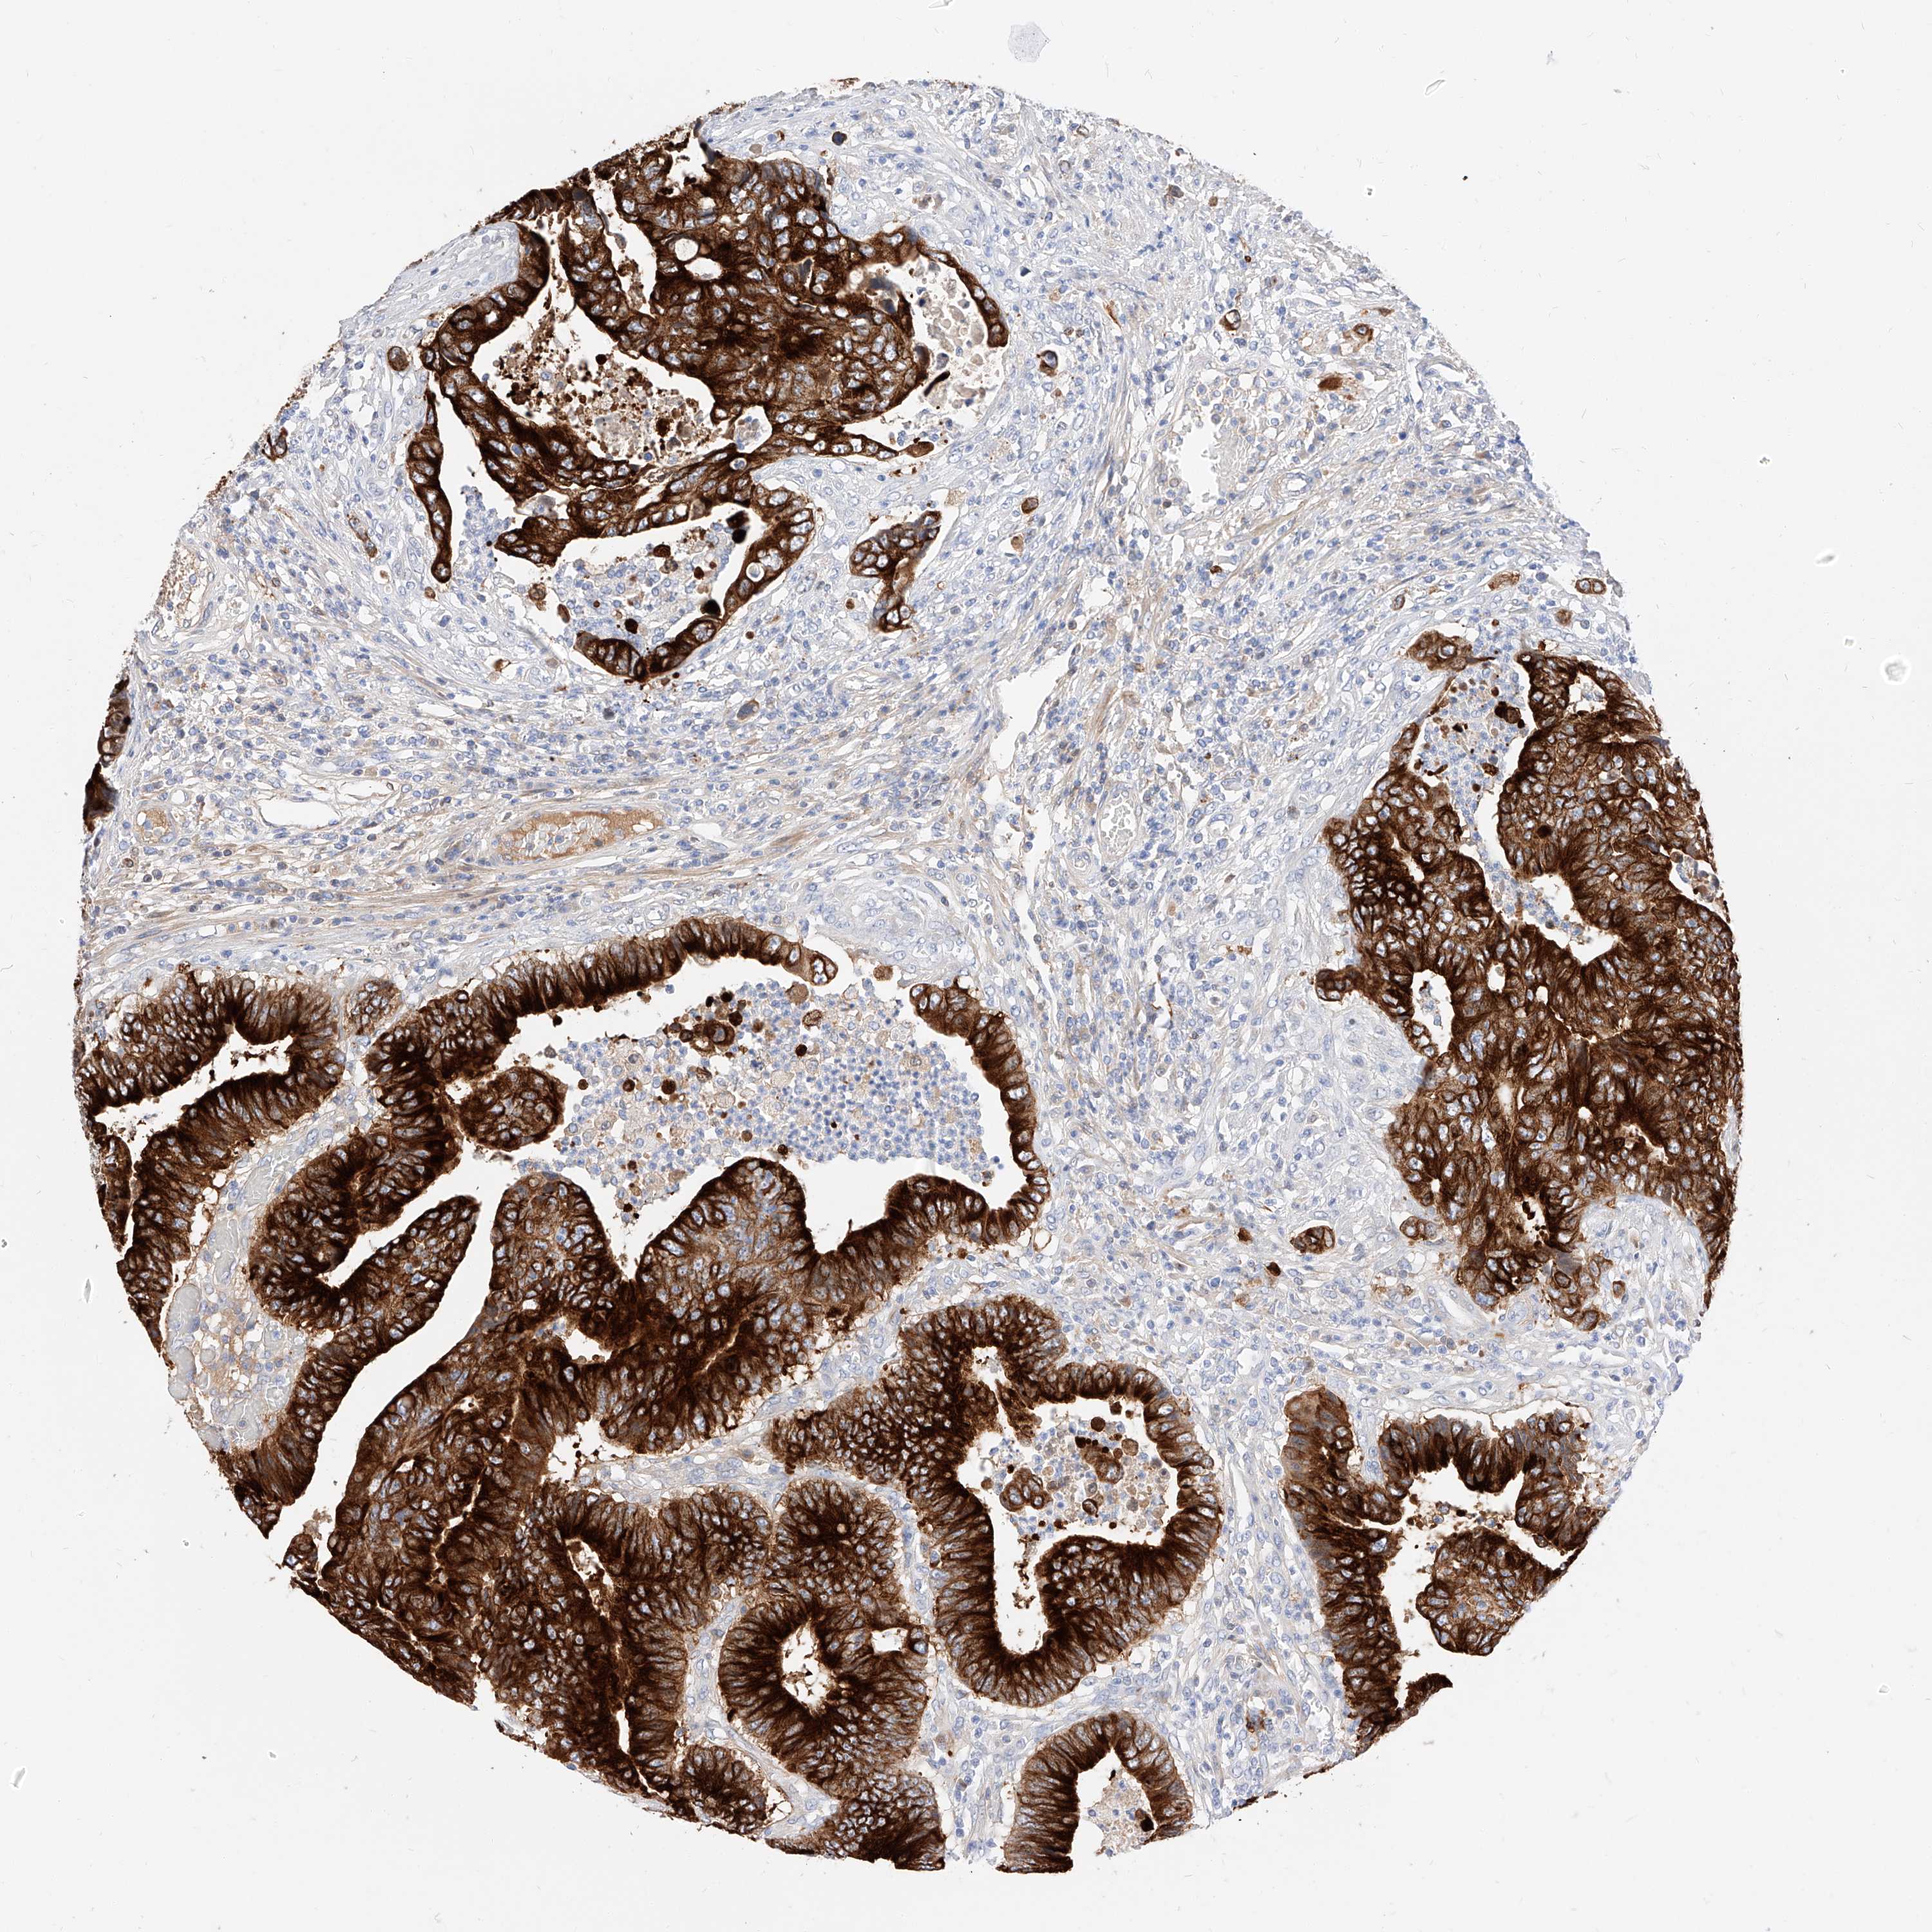

CANCER COLORECTAL CANCER Show tissue menu

Colorectal cancer

Human cancer

Colon adenocarcinoma